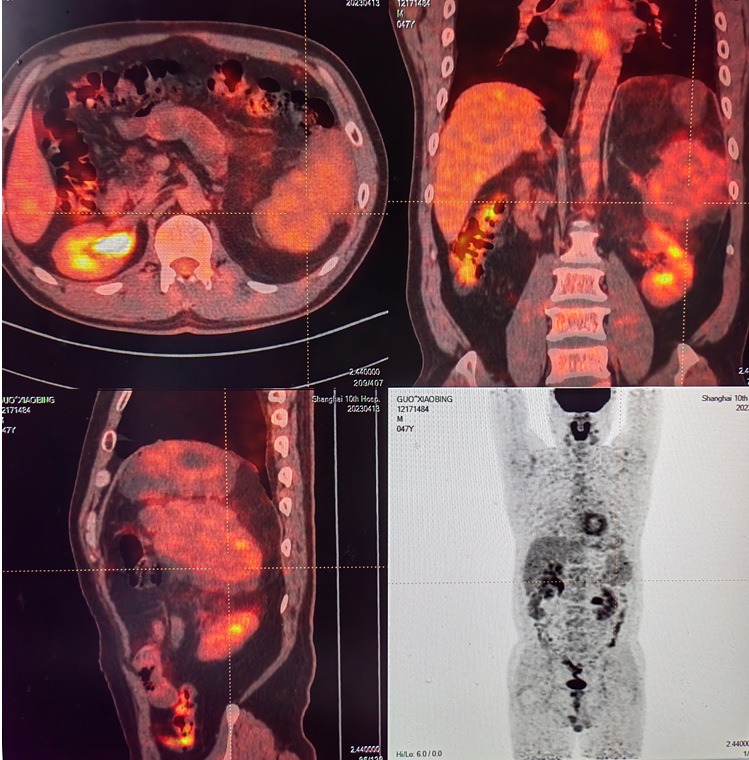

患者为47岁男性,8月前发现腹部包块,当时腹部CT提示左上腹巨大囊性占位,胃壁完全囊变型间质瘤可能,脾脏、胰腺尾部或左侧肾上腺来源囊性占位待排除。于当地医院行开腹探查+腹腔肿瘤切除+脾脏切除+肠粘连松解术,病理提示:去分化脂肪肉瘤。5月前复查腹部CT提示左上腹肿块,考虑肿瘤复发可能,当时未予相应处理。患者定期复查至今,入我科就诊后进一步完善PET-CT提示:腹膜后脂肪肉瘤术后,术区胰尾后方见团块状软组织密度影,大小105*65*82mm,分叶状,边缘光整,考虑脂肪肉瘤复发/转移,与左侧腹壁关系密切。经MDT讨论,拟行腹腔后肿瘤切除术。

术前PET-CT